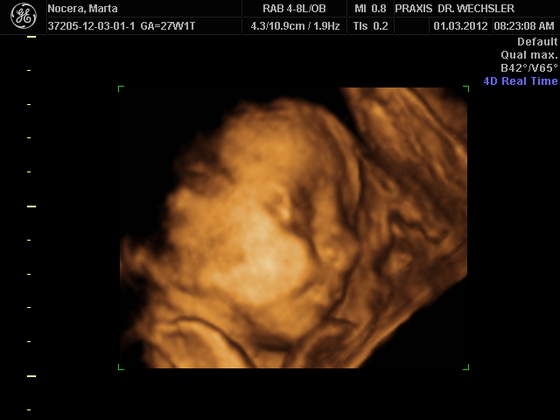

Karwiczki BBOOSSKKIEE ZDJĘCIA !!!!!!!!! ŚLICZNE MALEŃSTWO !!!!!

Aniu u nas tez calkiem wyraznie nie wyszly te zdjecia,nawet lekarz nie byl za bardzo zadowolony,ale fajnie,ze choc takie mamy,kosztowalo to nie malo bo 90 euro,maz twierdzi,ze duzo za drogo i spodziewal sie czegos lepszego,hmmm

za 3 miesiace bedzie lepiej widzial

nagranie mamy na dvd i do tego zdjecia 48 sztuk.